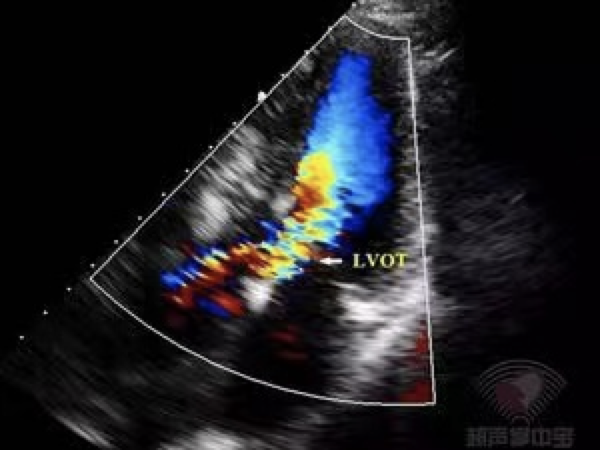

心尖五腔心切面CDFI:左室流出道呈五彩镶嵌花色血流信号。

心尖五腔心切面CW:左室流出道最大瞬时流速和压差增大(Vmax:462cm/s,PG:85mmHg),频谱峰值后移。CW示左室流出道峰值流速462cm/s,PG:85mmHg。

彩色多普勒超声心动图